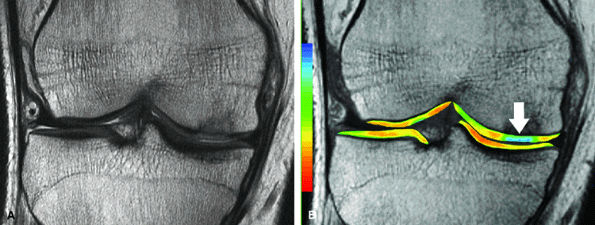

![]() |

FIGURE 7.15 ● (A) Coronal fast spin-echo MR image of the knee in a 15-year-old girl with a previous partial meniscectomy demonstrates mild fibrillation of the cartilage overlying the lateral tibial plateau (arrow). (B) Corresponding quantitative T2 relaxation time map of the femorotibial articular cartilage coded to capture T2 values ranging from 0 to 100 msec demonstrates prolongation of T2 values over the plateau, but with unexpected prolongation over the lateral femoral condyle (arrowheads), which appeared normal on standard fast spin-echo cartilage-sensitive imaging. Green and blue reflect longer T2 values, yellow intermediate, and orange the shorter values.